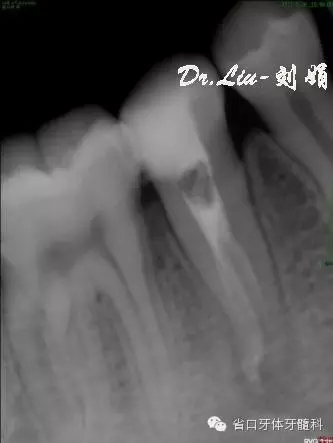

根管預(yù)備:顯微鏡下賽特力超聲ETB繼續(xù)去除根管上段及髓腔內(nèi)鈣化物,6#先鋒銼聯(lián)合pathfile銼和超聲逐步通根,測長:L=DB=MB=18mm,WAVE-ONE(Small)備根,紙尖干燥根管,氫氧化鈣糊劑暫封。

圖5:術(shù)中插尖片,見3根管